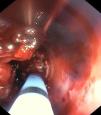

Paciente ingresado por distrés respiratorio de etiología infecciosa con necesidad de soporte de oxigenación por membrana extracorpórea venovenosa, por lo que se estableció anticoagulación. Complicación por hemoptisis masiva, ante lo que se realiza fibrobroncoscopia en la que se evidencian coágulos muy organizados desde tercio distal del tubo orotraqueal hasta carina principal, donde se aprecia coágulo compacto que procede de ambos bronquios principales y que se extiende a ramas lobares bilaterales (fig. 1). En TC de tórax se aprecia obstrucción completa de la vía aérea superior por material de alta densidad del tercio distal de la tráquea (fig. 2A) y ambos bronquios principales (fig. 2B) y el resto de la vía aérea distal, quedando únicamente permeable el tercio traqueal superior (fig. 2C). Se realiza fibrinólisis endobronquial con uroquinasa y lavado con fibrobroncoscopia tras cada instilación. Evolución favorable con mayor permeabilidad de ambos sistemas bronquiales y mejoría clínica que permitió retirada de oxigenación por membrana extracorpórea a los 21 días.